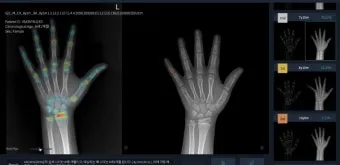

성장판은 하나의 문이 갑자기 '딱' 닫히는 것이 아닙니다. 손가락, 발가락, 손목, 발목, 골반, 척추 순으로 뼈 끝 쪽의 연골이 굳어져 가는 과정은 꽤 오랜 시간이 걸려요. 성장판의 닫히는 시기는 개인차가 매우 크답니다.

일반적으로 여성은 14-15세, 남성은 16-17세에 성장판이 닫히기 시작하지만, 완전히 닫히는 것은 만 19-20세경이에요. 하지만 여기서 중요한 건, 성장판 검사에서 '닫혔다'고 나와도 검사 오차가 있을 수 있고, 미세하게 남아있는 성장판으로 인한 성장 가능성이 남아있다는 점입니다.